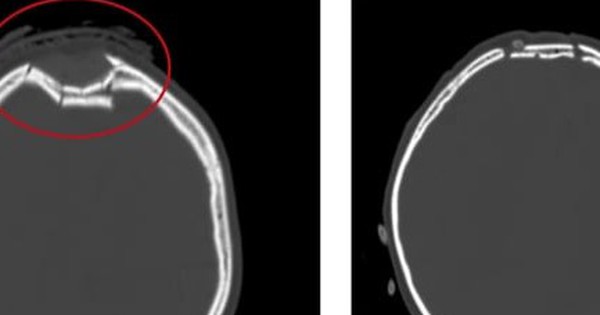

Bệnh nhân H.K.D (nữ, 53 tuổi) cho biết bà không bị chấn thương, không lao...